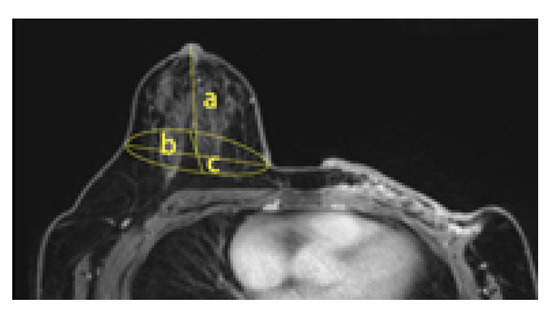

For MRI, breasts are in an ellipsoid shape drooping downwards, and thus the volume was measured with the assumption that it is in the ellipsoid shape. MRI images showed the shape of 1/2 ellipsoid sagging downward, and thus the 1/2 ellipsoid volume formula was applied (Formula (2)). This is the MRI volume calculation formula (Figure 7).

Figure 7.

The MRI volume calculation.